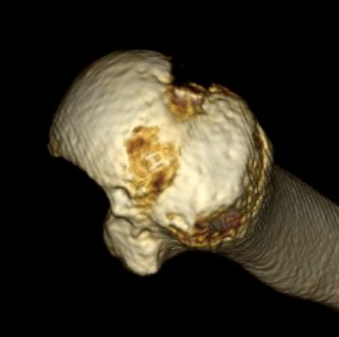

CT scan

Confirms dislocation

Reverse Hill Sachs

Humeral head defect

- caused by impaction of anterior humeral head on posterior glenoid

- intra-articular

- measured as a percentage of the articular surface